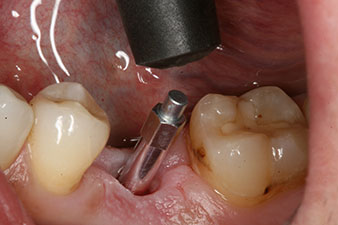

Implantat

Abb. 3: Nach Aufbereitung mit dem Implantmed Implantologiemotor wird ein Implantat (Durchmesser 4 mm, Länge 12 mm) bei einem Drehmoment von 43 Ncm maschinell eingeschraubt.

Nach gründlicher Entfernung des Granulationsgewebes wurde das Implantat wie geplant eingebracht (blueSky, bredent).

SmartPeg

Abb. 4: Eingeschraubter SmartPeg Messpfosten für die Bestimmung des Implantatstabilitäts-Quotienten mit dem integrierten W&H Osstell ISQ Modul.

Das Drehmoment beim maschinellen Einbringen war 43 Ncm. Zusätzlich wurde, nach Einschrauben eines speziellen, auf das Implantatsystem abgestimmten Mess-Pfostens (SmartPeg), der ISQ-Wert mit der Sonde des W&H Osstell ISQ Modul bestimmt.